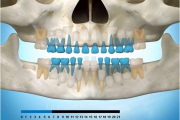

Esimeste molaaride (purihammaste) lõikumine

Esimeste molaaride (purihammaste) lõikumine. 1. molaaride ektoopilise lõikumise jälgimine. Ülemised ja alumised esimesed purihambad e. molaarid lõikuvad orienteeruvalt6-7-aastaselt piimahammaste rea lõppu. Enamasti lõikuvad samanimelised jäävhambad paaridena. Normaalne lõikumise Loe edasi »